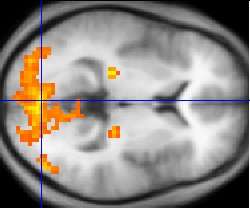

(Associated cortical regions involved in vision, touch sensation, and non-speech movement are also shown.)

Since then, there has been substantial debate over what linguistic processes these and other parts of the brain subserve.[26] Although Broca's and Wernicke's areas have traditionally been associated with language functions, they may also be involved in certain non-speech functions. There is also debate over whether or not there even is a strong one-to-one relationship between brain regions and language functions that emerges during neocortical development.[27] Research on language has increasingly used more modern methods, including electrophysiology and functional neuroimaging, to examine how language processing occurs.

Structural and functional imaging

There are several methods for detecting brain activity changes using three-dimensional imaging of local changes in blood flow. The older methods are SPECT and PET, which depend on injection of radioactive tracers into the bloodstream. A newer method, functional magnetic resonance imaging (fMRI), has considerably better spatial resolution and involves no radioactivity.[46] Using the most powerful magnets currently available, fMRI can localize brain activity changes to regions as small as one cubic millimeter. The downside is that the temporal resolution is poor: when brain activity increases, the blood flow response is delayed by 1–5 seconds and lasts for at least 10 seconds. Thus, fMRI is a very useful tool for learning which brain regions are involved in a given behavior, but gives little information about the temporal dynamics of their responses. A major advantage for fMRI is that, because it is non-invasive, it can readily be used on human subjects. Another new non-invasive functional imaging method is functional near-infrared spectroscopy.